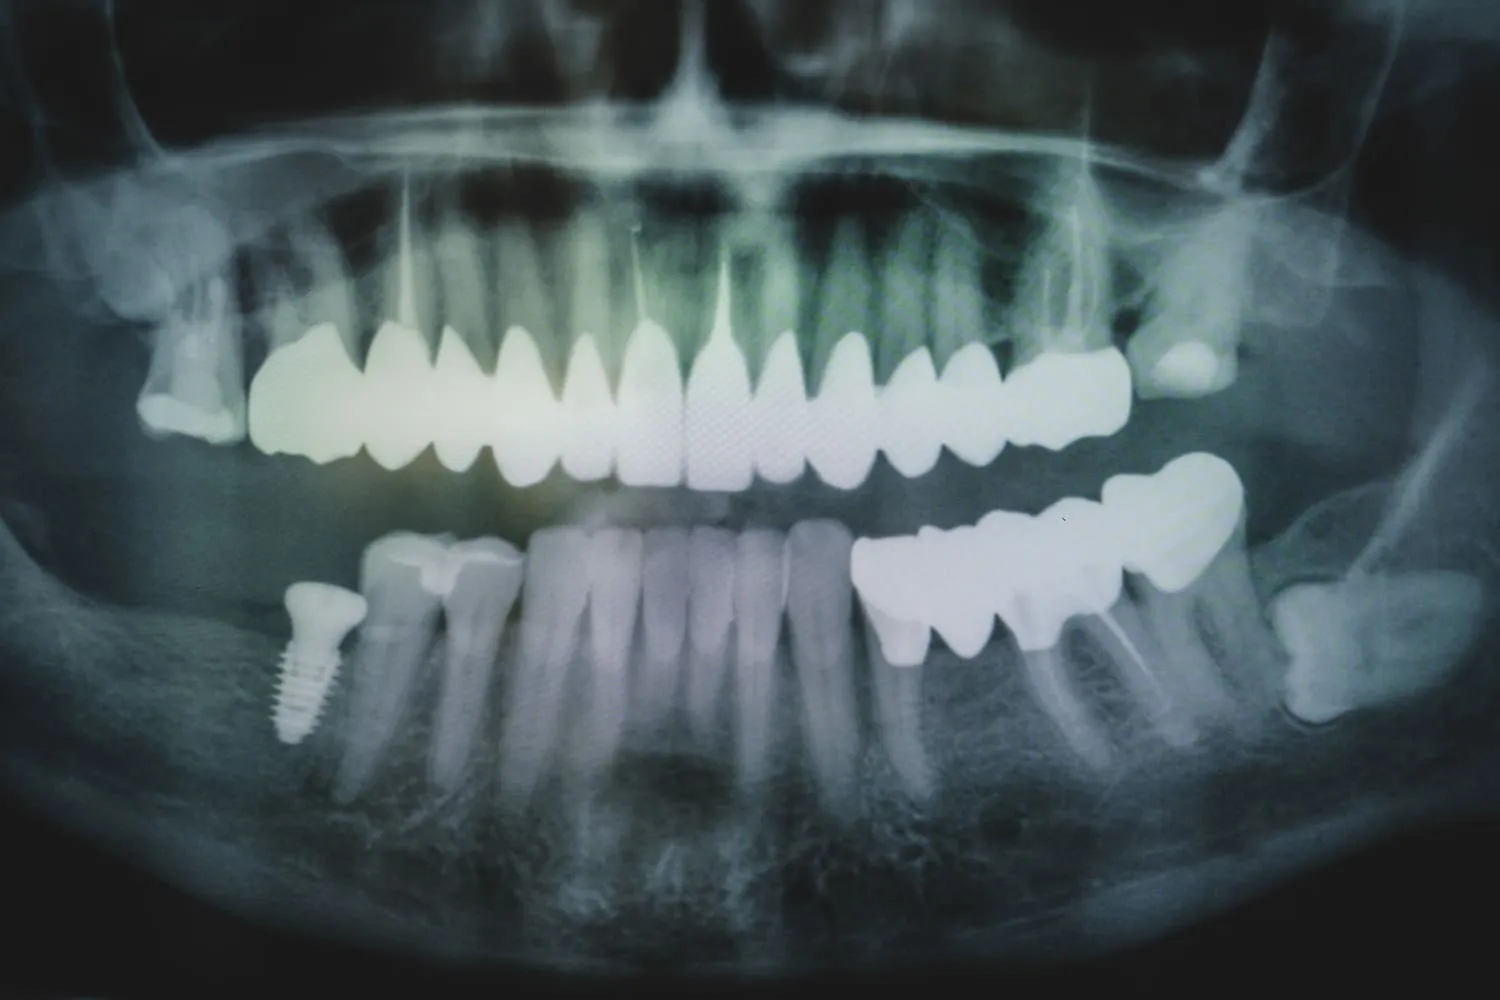

By using state-of-the-art equipment, such as the latest generation of 3D scanners, we can create extremely accurate images of the patient's mouth. These high-resolution images are not only extremely precise, but are also delivered in real time, significantly reducing the time required for diagnosis and treatment planning.

Scanning is a digital impression. Using a special micro-camera, a digital image of all the teeth is transferred to a computer within minutes, where a virtual image of the patient is created. Scanning is the equivalent of the old impression with silicone paste, which many patients found unpleasant.

The patient's new teeth (veneers, crowns, bridges) are designed on a computer screen in a virtual image of the mouth. With the help of special 3D software, an experienced prosthodontist can design teeth that perfectly match the patient's own teeth in very high magnification.

The previously designed teeth are milled using a special milling machine. The image of the new teeth is sent in digital form to the machine, which cuts them out of special ceramic blocks in about a dozen minutes. These blocks with specially selected hardness and color ensure the highest quality and durability of the new teeth. Thanks to the digital precision of the manufacturing process (up to 19 micrometers), the veneers, crowns and bridges fit perfectly in the patient's mouth.